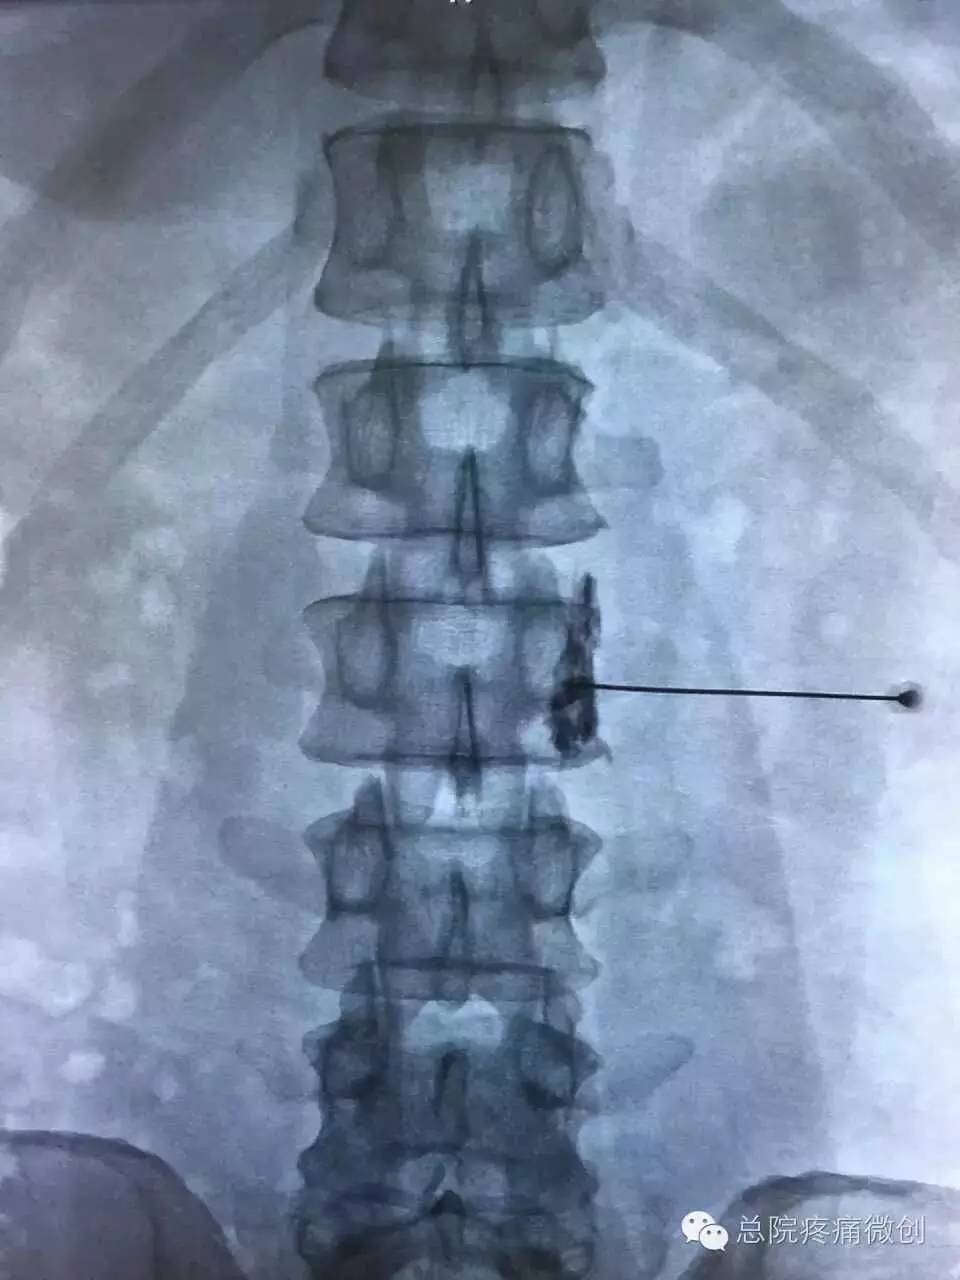

从疼痛的角度出发,针对支配血管的腰交感神经,通过神经阻滞,神经损毁等微创介入技术,可以为该类患者有效缓解疼痛。该治疗可强力止痛,解除血管痉挛,改善下肢循环。